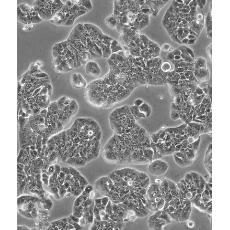

HT-29

中文名稱 人結腸癌細胞

形態特征 上皮樣

生長特性 貼壁生長

特征特性 該細胞是1964年由FoghJ用移植培養方法和含15%FBS的F12培養液從原發性腫瘤分離的。近來,已建株的培養細胞用含血清的McCoy's5a培養基培養。該細胞系在裸鼠中成瘤,也能在類固醇處理的地鼠中成瘤。該細胞可合成IgA、CEA、TGFβ結合蛋白和黏液素;表達尿激酶受體,但沒有檢測到血漿酶原活性;不表達CD4,但細胞表面表達半乳糖神經酰胺(HIV的可能替代受體)。該細胞系癌基因c-myc、K-ras、H-ras、N-ras、Myb、sis、fos陽性;p53基因過表達,并且在273位密碼子處發

培養條件 DMEM(高糖)+10%FBS